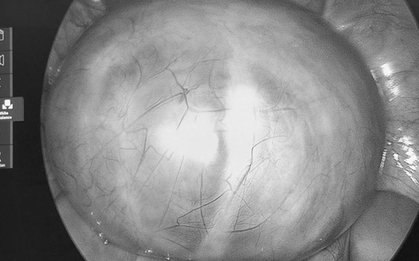

Bệnh nhân 15 tuổi nhập viện vì sốt và đau bụng dữ dội, các bác sĩ đã phẫu thuật cấp cứu thành công, cảnh báo về nguy cơ biến chứng nguy hiểm của ký sinh trùng.